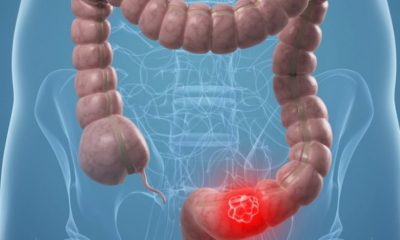

Ποιοι είναι οι συχνότεροι κληρονομικοί καρκίνοι;

23 Φεβρουαρίου 2019Η εργαστηριακή γενετίστρια του Εργαστηρίου Μοριακής Διαγνωστικής του Δημόκριτου Φλωρεντία Φωστήρα αναλύει τα αποτελέσματα των τελευταίων...